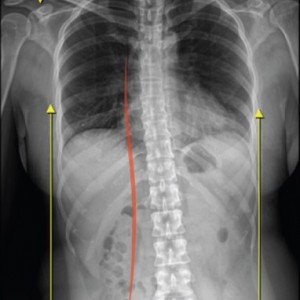

척추

척추측만증 또는 좌, 우 한쪽으로 기울어진 척추로 인해 체중이 한쪽 허리로 집중된다면 장기적으로 체중이 기울어진 쪽 허리에 뼈가 자라거나 퇴행성 변화가 빠르게 진행됩니다.